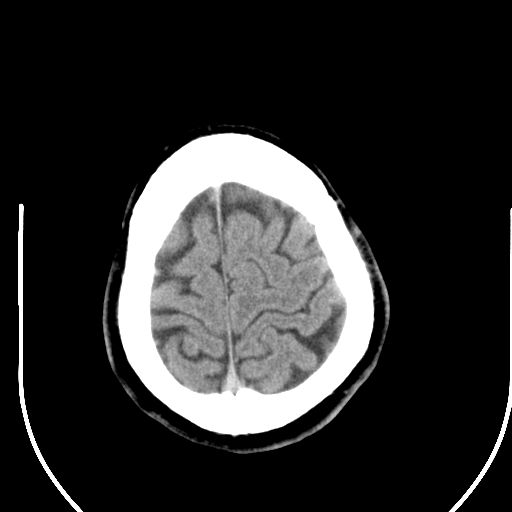

边缘清晰,没有占位效应,不像脑沟,结合ct值,软化灶可能吧

与脑沟没关系,小软化灶或陈旧性感染吧!

看样年纪不小了直接报腔梗,当然你要想报软化灶也是一样的

考虑右侧额叶巨腔隙灶;建议必要时行mri检查。

软化灶。